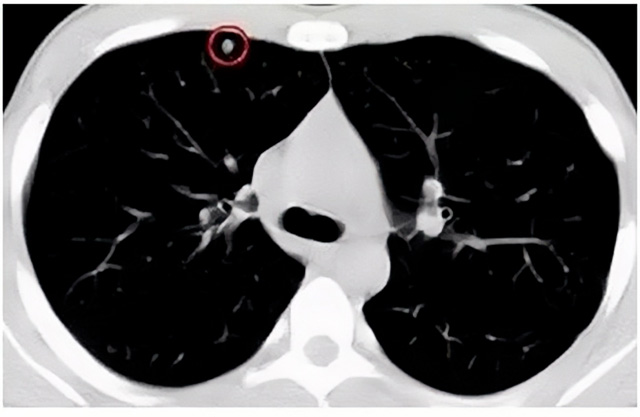

移動(dòng)CT體檢車可以檢查肺結(jié)節(jié)發(fā)現(xiàn)早期肺癌

移動(dòng)CT體檢車可以做肺部檢查。隨著多層螺旋CT肺部低劑量掃描的臨床應(yīng)用,目前很多人選擇肺部CT作為常規(guī)檢查項(xiàng)目,較大地提高了肺結(jié)節(jié)的檢出率。如果檢查發(fā)現(xiàn)肺部有肺結(jié)節(jié)是磨玻璃型的,小于5mm的微小結(jié)節(jié),大部分都是良性的。如果達(dá)到1CM以上的,很有可能有肺癌的機(jī)率。根據(jù)其內(nèi)密度不同可分為磨玻璃結(jié)節(jié)、實(shí)性結(jié)節(jié)、部分實(shí)性結(jié)節(jié)。根據(jù)其大小可分為肺大結(jié)節(jié)、小結(jié)節(jié)和微小結(jié)節(jié)。如果是炎癥性肺結(jié)節(jié),幾個(gè)月后復(fù)查有變化變小就不用做手術(shù)。如果CT再次復(fù)查結(jié)節(jié)沒有變化,沒有縮小就需要升級做病例檢查。病理檢查的確診性是最高的。是有沒患癌的標(biāo)準(zhǔn)。檢查發(fā)現(xiàn)早的話,規(guī)范手術(shù)治療,手術(shù)后5年的存活率很高的。肺癌這個(gè)要早發(fā)現(xiàn)早治療。

現(xiàn)在的移動(dòng)CT體檢車的分辨率比X光高,CT掃描的圖像越來越薄顯像更清晰,檢查更準(zhǔn)確。得到了普及,肺結(jié)節(jié)的測出率很高的。但是顯浩告訴大家,肺結(jié)節(jié)不等于肺癌。雖然很多是良性,但是很多肺癌都是肺結(jié)節(jié)發(fā)展來的。 必須定期檢查復(fù)查。磨玻璃結(jié)節(jié),肺癌的機(jī)率較高。肺癌是惡性腫瘤病死率最高的。除了環(huán)境,遺傳,等因素。吸煙,從事煙霧工作行業(yè)的人員比較危險(xiǎn)。發(fā)病比例高。肺部疾病早發(fā)現(xiàn)早治療,依舊是肺部疾病的治療標(biāo)準(zhǔn)。

一旦CT檢查發(fā)現(xiàn)肺結(jié)節(jié),若不規(guī)律復(fù)查,檢查等同于白檢。所以在復(fù)查中,如果結(jié)節(jié)中發(fā)現(xiàn)有增大的趨勢,或大小發(fā)生了變化,我們必須提請注意及時(shí)治療,不要掉以輕心。移動(dòng)CT體檢車的普及化,讓肺部檢查更準(zhǔn)確更高效。發(fā)現(xiàn)肺結(jié)節(jié)時(shí),及時(shí)就醫(yī)并進(jìn)行專業(yè)評估是確保準(zhǔn)確分類和采取適當(dāng)措施的關(guān)鍵。